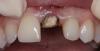

zybnaya feya Опубликовано 29 мая, 2013 Поделиться Опубликовано 29 мая, 2013 (изменено) Всем доброго дня) Давно тут не появлялась,соскучилась за вами всеми и работой Случай мой возможно банальный,но все же Пациентке 3,5 года назад были установлены одиночки е.мах на 11,21,22 Пациентка проходила с ними 3 месяца. Потом произошла травма,треснула коронка 21 . Пац к доктору не обратилась и проходила с трещиной 3 года,пока та не прокрасилась. Может ходила бы еще,но произошла расцементировка СВШ на котором все это добро держалось. Пришлось клеить на жвачку и идти к доктору) Вот такая она ко мне явилась.http://s017.radikal.ru/i410/1305/08/36eecc493b8b.jpg http://s020.radikal.ru/i706/1305/72/f53c6b2073f2.jpg Самая большая сложность состояла в том,что 21 пережил 3 резекции! Длины его корня осталось всего 13мм с диаметром на "апексе" больше 110 Плюс как вы видите пародонтальный карман. Пациентке рассказала о всех подводных камнях.От удаленя она отказалась. Корень неподвижен. Поехали... http://s57.radikal.ru/i156/1305/81/84012f79076d.jpg Апекс закрыт МТА анжелюс который http://s017.radikal.ru/i433/1305/22/07afbb949b4b.jpgНа следующий день проверка мта уз. Все ок. http://s020.radikal.ru/i700/1305/52/1116c7655ba5.jpg http://i011.radikal.ru/1305/e4/d15592222c4f.jpg Снимаем оттиск,бла бла бла... фиксируем ДЦ вкладку http://s47.radikal.ru/i115/1305/13/8d2d0a6f213d.jpg http://s019.radikal.ru/i632/1305/2f/66627a42f173.jpg Времянка (так себе)http://s002.radikal.ru/i197/1305/3c/1fd0205bceb5.jpg После фиксации короночки 21 е.мах http://s48.radikal.ru/i119/1305/10/0efd7e4c8173.jpg http://s018.radikal.ru/i526/1305/0e/836ce54c2334.jpg Соотношение коронка-корень, коропковая-корневая культя конечно критическое. http://s018.radikal.ru/i502/1305/f8/844cedf2543a.jpgДоктор осозает всю тяжесть сиуации,пац нет ,но довольна . Это наверное главное. Хорошо когда люди улыбаютсяhttp://s020.radikal.ru/i723/1305/c0/b4468c881d39.jpg Изменено 29 мая, 2013 пользователем zybnaya feya 9 Ссылка на комментарий